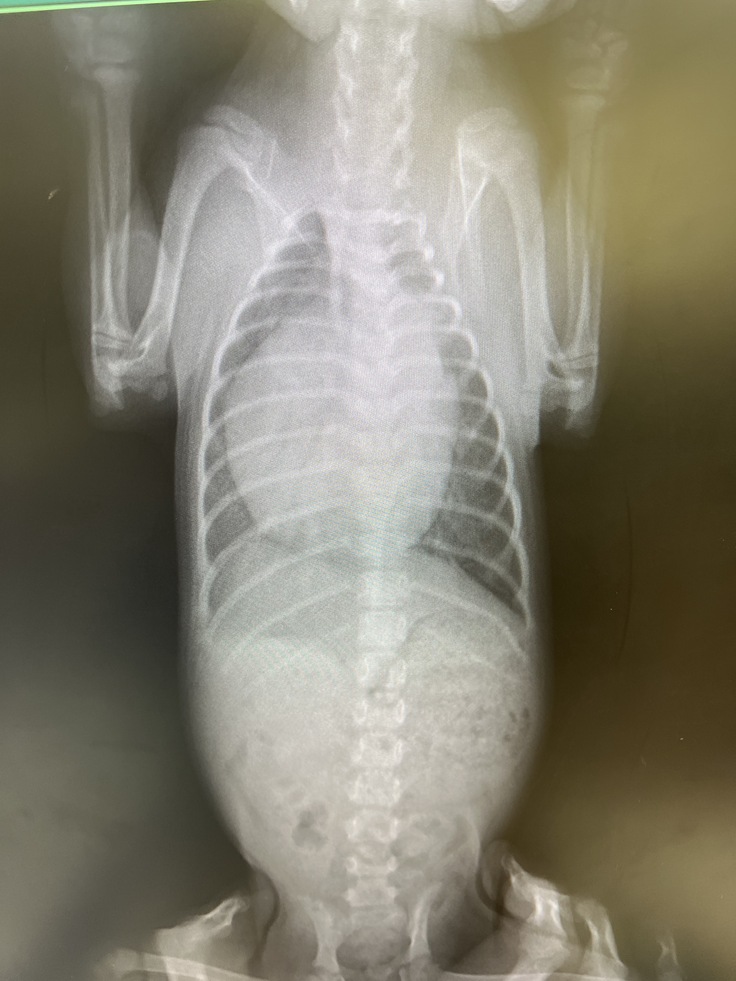

↑まる子のレントゲン

レントゲンも通常の子に比べると(特にまる子は)明らかに心臓が大きく異常な状態です。同じ病気でも初期の場合は心臓の拡大は認められないため、レントゲンからも今の病態は比較的進行した状態だということが分かります。